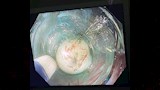

نجحت وحدة المناظير بكلية الطب جامعة حلوان في إجراء أول عملية من نوعها باستخدام منظار الموجات فوق الصوتية لتشخيص واستئصال ورم بالمريء في جلسة واحدة، دون الحاجة إلى إجراء فتحات جراحية، بمستشفى بدر الجامعي.

وتمت العملية في غضون 30 دقيقة باستخدام تقنية مناظير الفراغ الثالث؛ حيث تم تحديد نوع الورم ومكانه وحجمه ومنشئه، عبر منظار الموجات فوق الصوتية، ثم استئصاله مباشرة في نفس الجلسة. وتميزت العملية بتوفير الوقت على المريضة وتجنيبها مخاطر التخدير المتكرر؛ حيث تم خروجها من المستشفى خلال 24 ساعة في حالة صحية ممتازة دون أي مضاعفات.

وأجريت العملية تحت إشراف الدكتور شريف البحيري، مدرس الباطنة العامة بكلية الطب واستشاري المناظير التداخلية ومناظير الفراغ الثالث، والذي تلقى تدريبًا متخصصًا على هذه التقنية المتقدمة في جامعة كاتب أتاتورك بتركيا خلال مهمة علمية من جامعة حلوان.